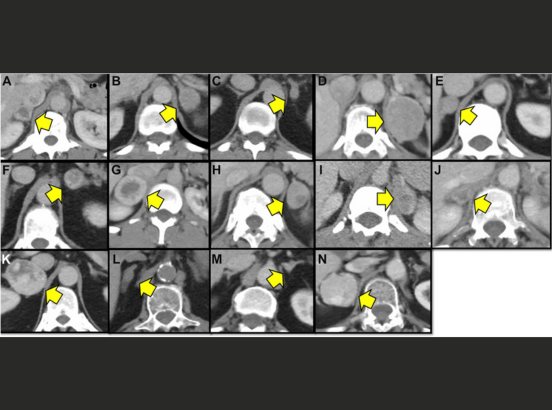

Figure 1: Adrenal protocol CT scans of 14 pheochromocytoma patients, showing pheochromocytomas (yellow arrows) often misinterpreted by other hospitals as adenomas, atypical lesions, or possible metastases.

In the study, standard CT scans showed these tumors had higher density (often 20–37 Hounsfield units) than typical adenomas, but reports sometimes overlooked this key detail. Specialized "adrenal protocol" scans with multiple phases of contrast can help clarify, yet they're not always used at other hospitals.